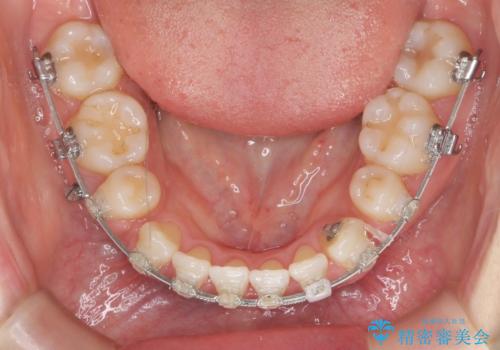

八重歯 上下の正中のずれ 40代で抜歯矯正

- 八重歯と上下の正中のずれを気にして来院。

上の前歯の正中が右にずれていました。

小臼歯抜歯を行い、ワイヤー矯正を行いました。

時間はかかりましたがしっかり治療することができました。